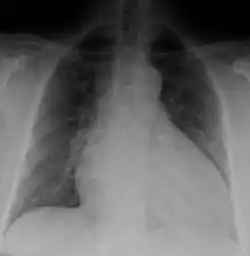

Dilated cardiomyopathy on CXR

Generalized enlargement of the heart is seen upon normal chest X-ray. Pleural effusion may also be noticed, which is due to pulmonary venous hypertension.[28]